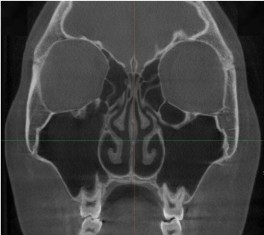

삼성드림이비인후과의 누적된 데이터로 비중격만곡증을 분석합니다.